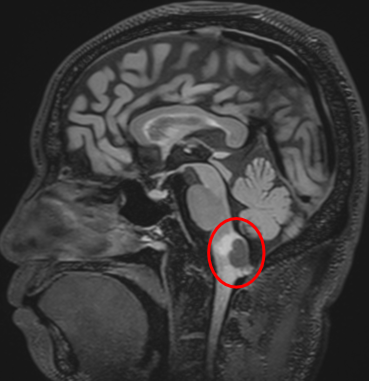

与上述病例形成对比的,是华裔德国精英高管W先生的故事。虽然都是延髓血管母细胞瘤,但W先生的结局完全不同。W先生因持续加重的身体麻木就医,检查发现延髓背侧存在血管母细胞瘤,好在没有出现更严重的急性事件。血管母细胞瘤的手术治疗效果通常不错,偏偏这种肿瘤血供量极大,手术难度不小。尤其是长在延髓上的病变,术中稍有不慎就可能影响患者的呼吸、心跳和血压。W先生和家人决定,既然要治,就一定要找最好的医生。

通过INC国际神经外科,W先生联系上了巴教授。巴教授的评估是:如果用1到10分来评价这台手术的难度,他给它打5到6分。言下之意是,有些医生认为这类手术风险极高,甚至根本无法开展,但对他来说这是常规手术。术前规划、麻醉方案、手术体位、术中操作的每一步精准执行、术后管理——任何一环出现疏漏,都可能带来无法挽回的后果。最终,W先生选择在北京天坛医院由巴教授主刀手术。

巴教授提到,术中神经电生理监测就像一个"扫雷器",能实时追踪各种神经电信号。在巴教授看来,没有电生理监测的脑外科手术是不人道的。业内有一句流行的话:监测本身很简单,复杂的是判断监测结果。巴教授在手术中"双肩挑"——一边全神贯注进行显微操作,一边在关键步骤主动询问监测数据的变化,这种模式让主刀医生能够在术中实时保护正常的神经功能。2025年8月13日,巴教授作为北京天坛医院神经外科外籍专家,经枕下正中入路,成功为W先生实施了延髓血管母细胞瘤全切手术。